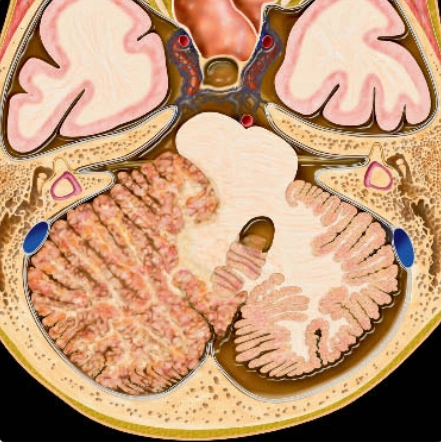

U nguyên tủy bào (Medulloblastoma)